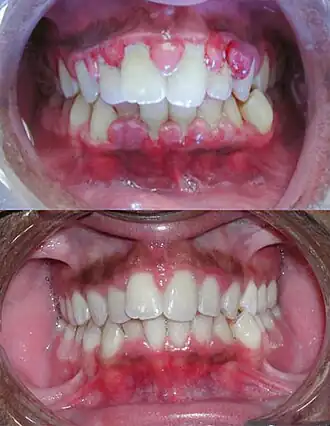

| Gengivite severa antes do tratamento na imagem de cima e depois do tratamento por debridamento mecânico na imagem de baixo. | |